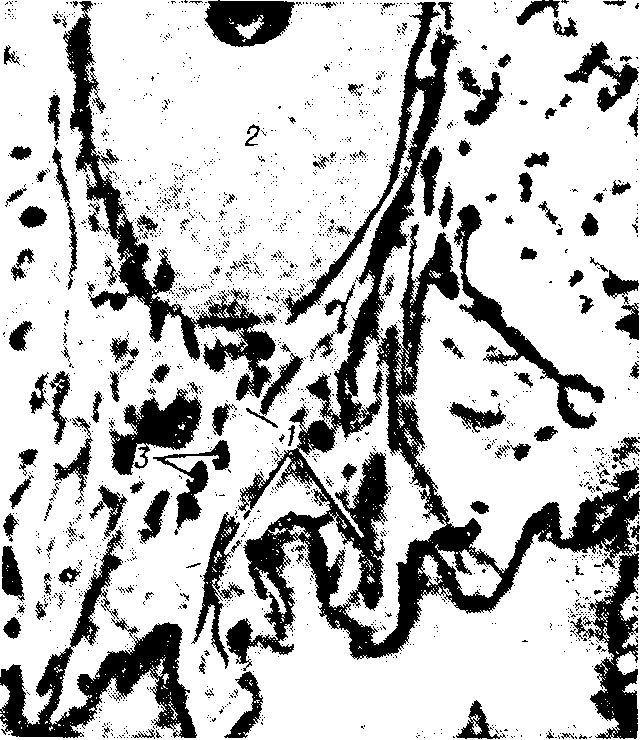

Рис. 3. Электронограмма базальнои части клетки из базального слоя эпидермиса человека: 1 —тонофибриллы, 2-ядро, 3-глыбки пигмента меланина

пидермис состоит из пяти слоев: назального, шиповатого, зернистого, блестящего, рогового. Базальный слой (stratum basalе) представлен одним рядом палисадообразно расположенных на базальной мембране призматических клеток (базальных эпидермоцитов — epidermocytus basalis) с ядрами, ориентированными перпендикулярно баззльной мембране. В их цитоплазме имеется большое количество тончайших нитей — тонофиламентов, собирающихся в пучки— тонофибриллы (опорные волоконца), видимые уже в световом микроскопе, а также глыбки (зерна) пигмента меланина (рис. 3). Базальные клетки закреплены и базальной мембране пальпеобразными выростами с полудесмосомами. Соседние эпидермоциты связаны друг с другом взаимопроникающими впячиваниями и десмосомами. Размер межклеточных промежутков около 10 мм.Базальная мембрана имеет толщину 25—35 мм состоит из узкой осмиофильной цитоплазматической мембраны базальных клеток и более широкой собственно базальной мембраны средней электронной плотности, от к-рой к цитоплазматическим отделам идут тонкие перемычки. В цитоплазматичсской мембране имеются полу-десмосомы, к к-рым подходят тонофибриллы.